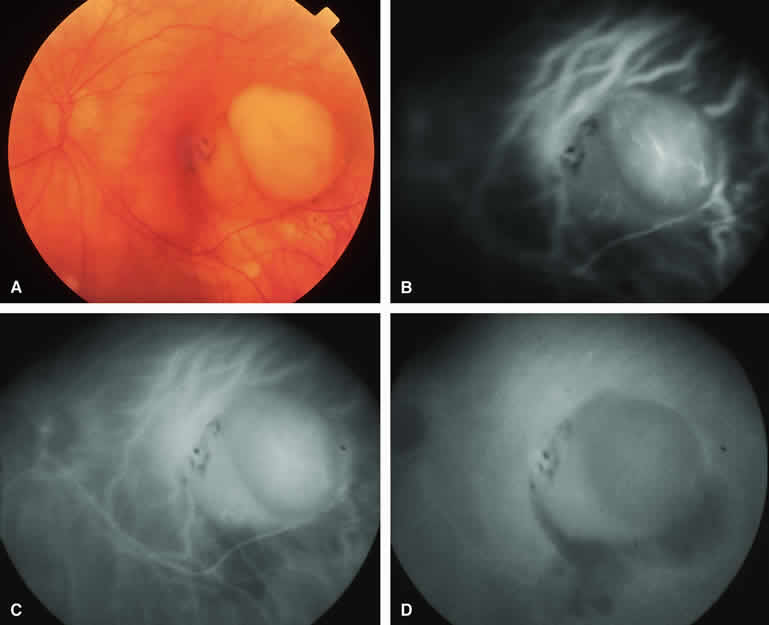

Typical Melanotic Choroidal Nevus

Fluorescein angiography of a typical choroidal nevus with bland surface features (see Fig. 1) shows the entire lesion to be hypofluorescent relative to the adjacent uninvolved choroid throughout the study. No large-caliber choroidal blood vessels are usually identifiable within the lesion. The retinal vasculature overlying the lesion appears well defined and normal on fluorescein angiography.

ICG angiography of a typical melanotic choroidal nevus (see Fig. 2) shows better definition of the basal area of the lesion than does fluorescein angiography. The entire lesion appears completely and uniformly dark throughout the ICG angiogram. Only the larger retinal blood vessels overlying the nevus are usually demonstrated on ICG angiography.